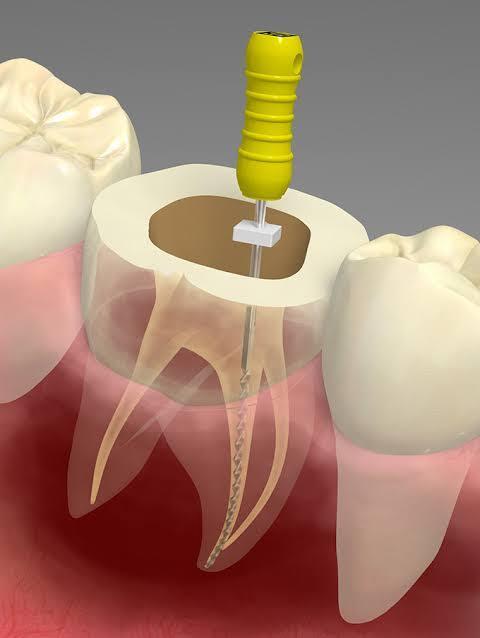

根管治療で大事なことは、「根管の中を無菌化すること」です!

無菌化できない根管治療を受けると、いずれ根の先が膿んでしまいます。

• マイクロスコープと呼ばれる根の中を見る顕微鏡で根の状態を直接目視できる。根の状態や汚染されていないかなど

マイクロスコープを用いるメリット

• ミクロレベルの患部も正確に診断することが可能となり、歯の神経や血管などの根管の内部から再発を繰り返す原因となっていた虫歯の兆候まで識別できるようになります。